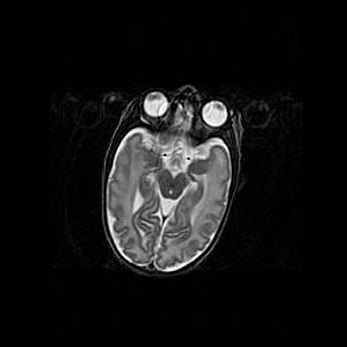

Наружная гидроцефалия с возможной атрофией височных областей.

Возраст: 28 дней

Вес: 3670 г

Пол: мужской

Окружность головы: 38 см

Срок гестации: 40 недель

Гидроцефалия головного мозга у новорожденных – это заболевание, которое характеризуется скоплением избыточного количества спинномозговой жидкости в желудочковой системе головного мозга в результате затруднения её перемещения от места выработки к месту поглощения в кровеносную систему или вследствие нарушения абсорбции. При открытой наружной форме гидроцефалии у новорожденных расширяются и переполняются субарахноидные пространства.

При нормотензивных  формах,  которые,  как  правило,  являются  следствием  перенесенных ишемических  повреждений  паренхимы  мозга,  возможно  сочетание микроцефалии  с нормотензивной гидроцефалией. В основе данных изменений лежит атрофия больших полушарий с преимущественной  локализацией  в  лобно-височных  областях.